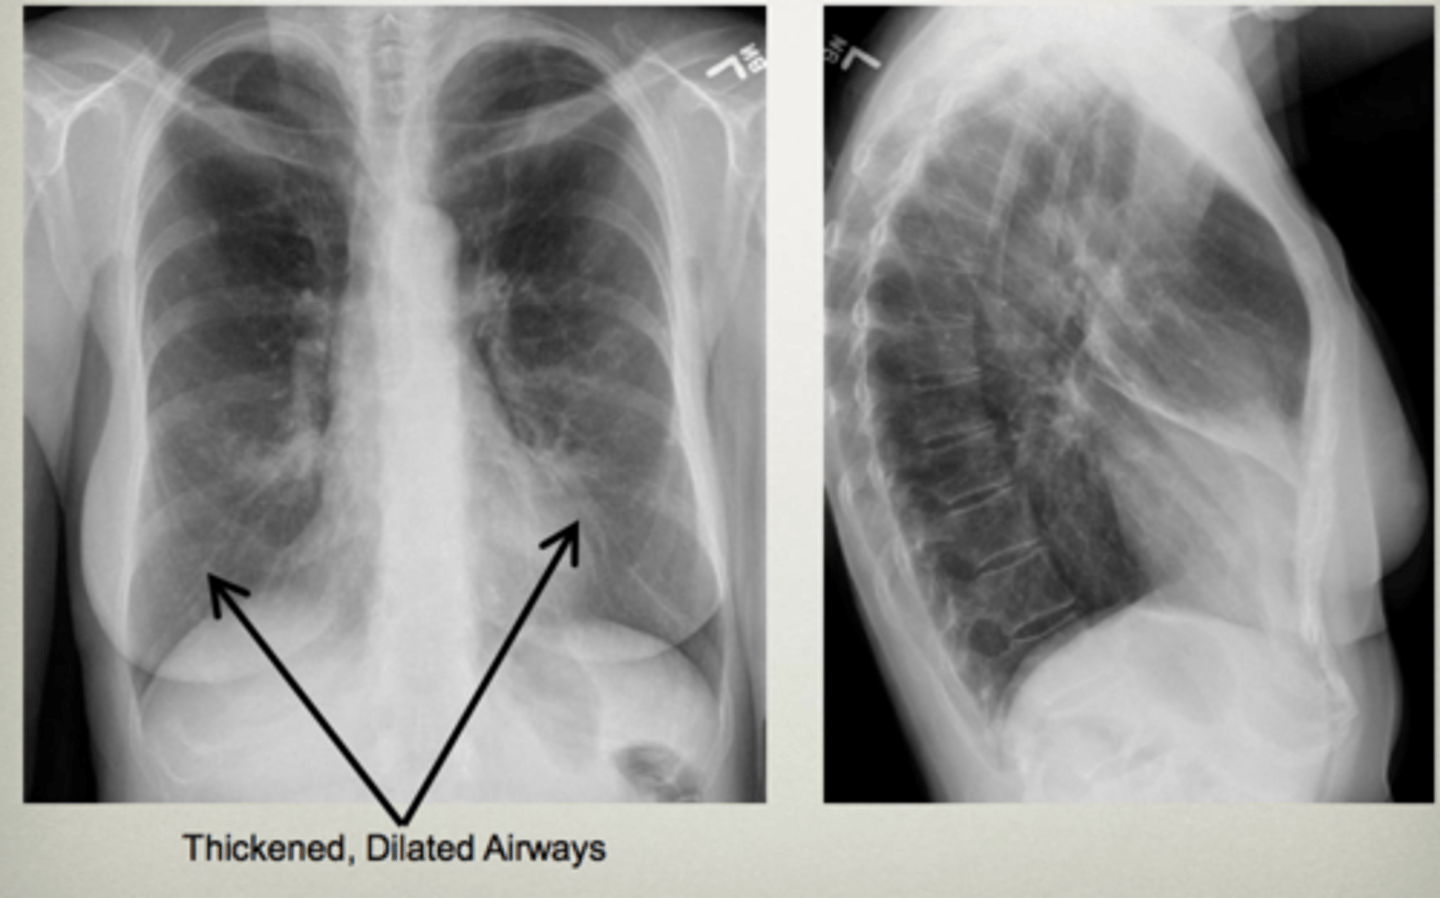

Walls of the bronchi thickened by inflammation or infection, may be diffuse or focal

Bronchiectasis

CXR in affected individuals is often normal or shows non-specific findings

Bronchiectasis

Bronchiectasis

Tram track lines

Asthma (hyperinflation with tram lines)

asthma